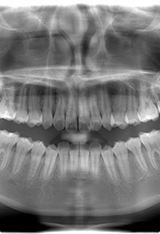

FLOW 1-2

レントゲン検査

パノラマレントゲンやCT検査など、歯茎の中の骨状態を把握するのにレントゲン検査が必要になります。細かく精密に検査が必要な方は、小さいレントゲンを細かく撮らせていただく場合もあります。